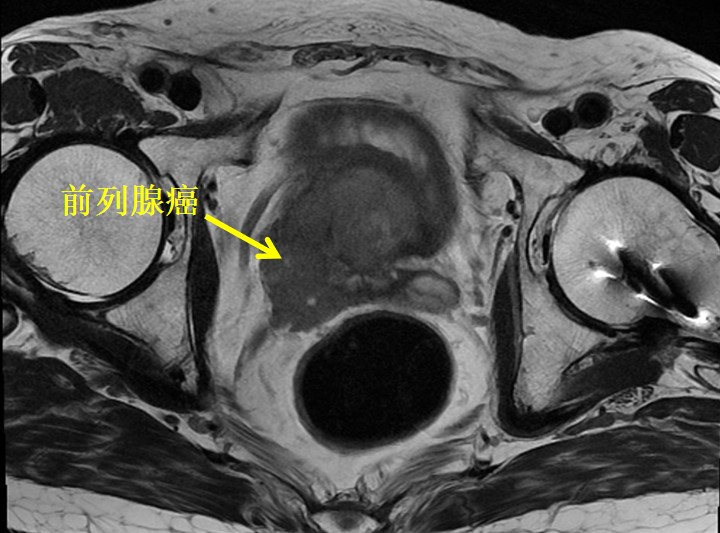

患者为60岁男性,体检时发现PSA升高,指标>100ng/ml。一周后,慕名从浙江至我院浦金贤教授专家门诊就诊。磁共振提示:前列腺中央带腺体及外周带前列腺癌,建议穿刺活检,盆腔左侧淋巴结增大。我院穿刺病理提示:前列腺腺癌,Gleason分级评分4+4=8分,双侧受累。患者PSA升高明显,磁共振下显示盆腔淋巴结肿大,考虑肿瘤负荷较高,预后不佳。浦金贤教授决定行腹腔镜下根治性前列腺切除+盆腔淋巴结清扫术,力求彻底切除肿瘤,提高远期生存。

前列腺癌是中老年男性常见的恶性疾病,局限性前列腺癌首选手术切除,可达到根治效果。但前列腺癌患者大多为中老年病人,常有多种合并症,手术治疗有较大风险。研究发现前列腺癌根治术后肿瘤切缘阳性率达6%-50%并且与生化复发有关。如何在术中精准实时定位前列腺癌病灶是目前一大难题。目前研究聚焦于肿瘤特异性的荧光造影剂成像技术下术中实时导航手术,术中实时精确区分肿瘤组织和正常组织。研究发现,PSMA在前列腺癌细胞表面过表达,目前已经被用于前列腺癌正电子发生断层成像(PET-CT)和术后治疗的靶点。国外已有靶向PSMA的荧光造影剂用于前列腺癌患者的荧光导航手术,在手术中可显著增强前列腺癌原发灶、手术切缘、切缘残余癌灶和淋巴结转移灶的可视性,其安全性和可行性得到证实,目前国内尚无相关应用报道。